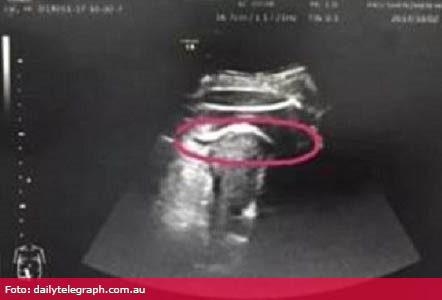

La ora 10:00, Zhang a mers la Departamentul de Urgență al Spitalului Universitar din Beijing, Shenzhen, din China, scrie site-ul oficial al instituției. Aceasta acuza o durere insuportabilă, iar medicii au observat că ceva nu e în regulă cu tensiunea arterială, pulsul și respirația mamei. Doctorii aveau bănuiala că uterul femeii s-a rupt și i-au efectuat o ecografie.

Investigația a arătat că fătul a lovit cu piciorul peretele uterului în partea dinspre abdomenul mamei, explică medicii.